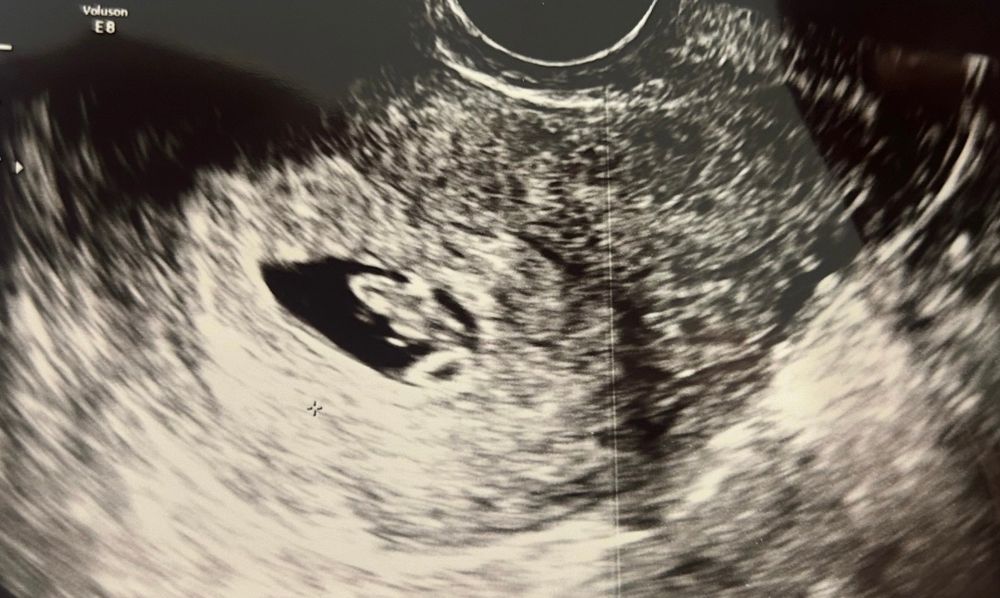

Беременность 7 недель 2 дня

Всем привет, сегодня для своего успокоения пошла на узи, у нас все хорошо, эмбриончик растет, сердечко бьется))

Теперь я спокойна, и до первого скрининга больше ничего сдавать и делать узи не буду)) скрининг будет в середине января))